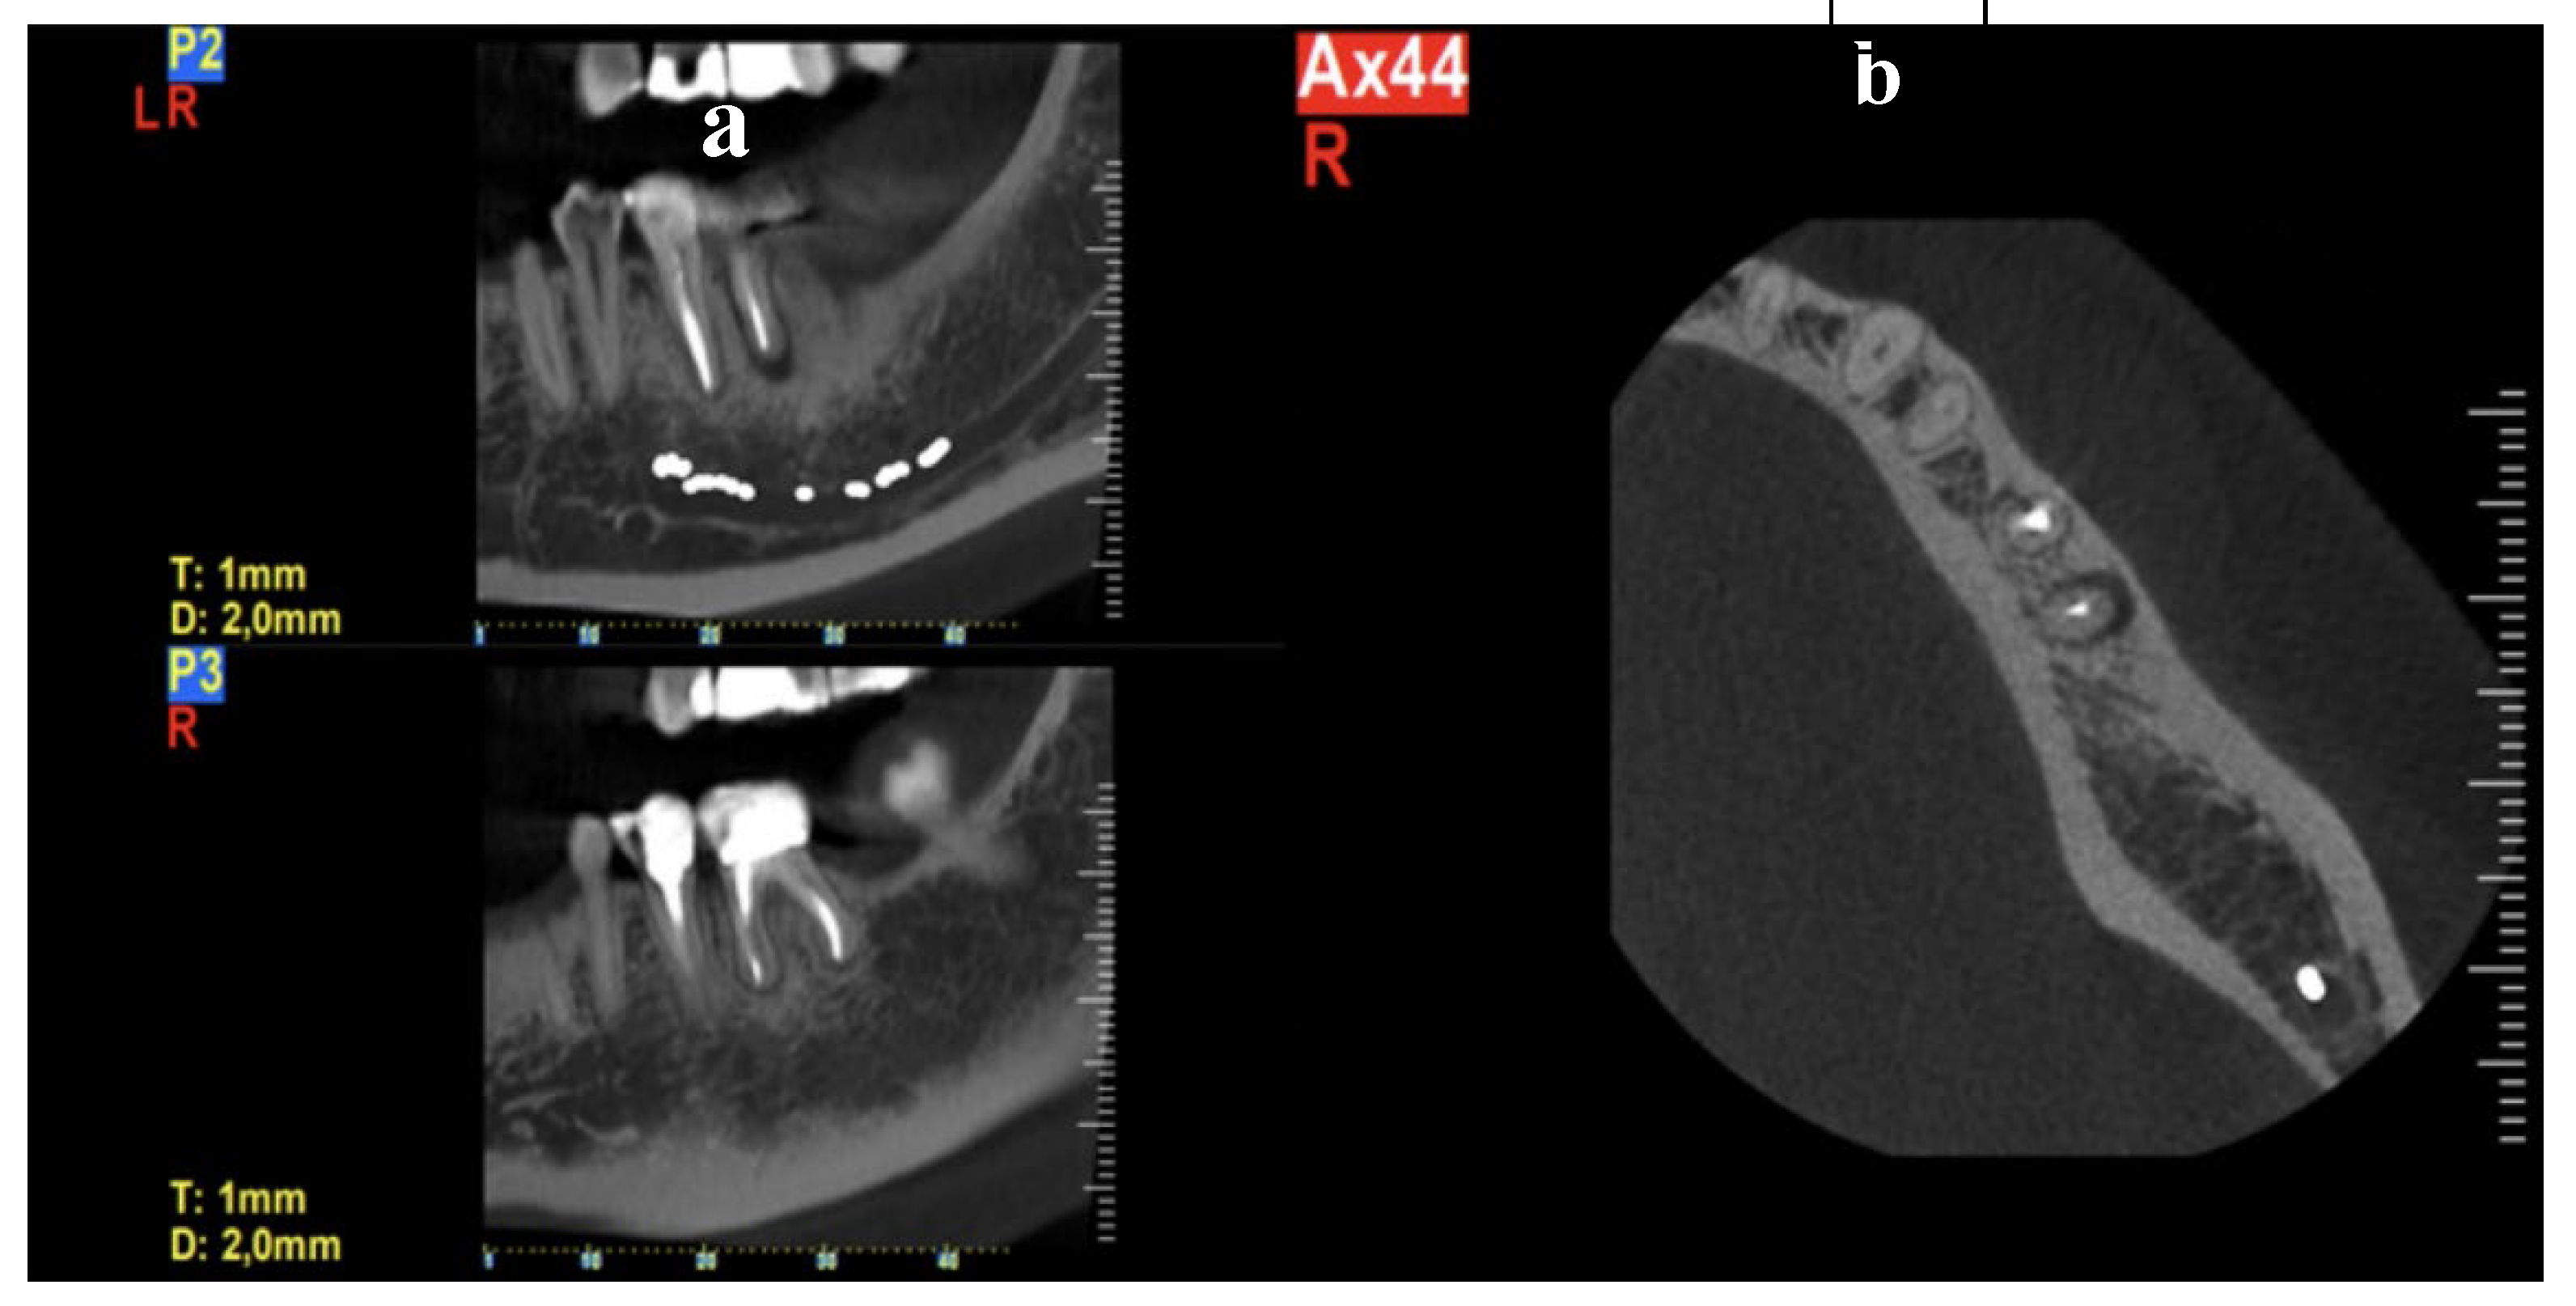

The clinical examination in this area revealed that the gingiva in the molar region was moderately inflamed, percussion of the molars elicited a slight sensitive reaction on tooth #37 and no mobility was present. However, a deep narrow pocket (16mm) in the buccal aspect of the mesial root of the second molar (#37) was found upon probing. A periapical radiograph in this area showed a J- shaped radiolucent area in the mesial root of the #37 tooth extending from crest of the alveolar ridge to the apex of the tooth (Figure 3). Based on these clinical and radiographic findings a CBCT examination of the lower jaw was suggested to evaluate firstly if there is a vertical fracture on mesial root of tooth #37 and secondly to verify the consistency and dimensions of the bone for implant placement in the region of #46-#47. (Figure 4 and Figure 5). From the CBCT evaluation the suspected vertical root fracture in the mesial root and the suitability for implant placement were confirmed [34] (Figure 4).

Figure 4. CBCT section of tooth #37 illustrating the pattern of bone resorption alongside the mesial root.

Figure 12. a) Coronal view, radiolucency around the mesial root b) Axial view, a very localized, angular, fissure-like pocket on the buccal surface of the mesial root of tooth 36 raises suspicion of a possible crack or fracture in the mesial root.